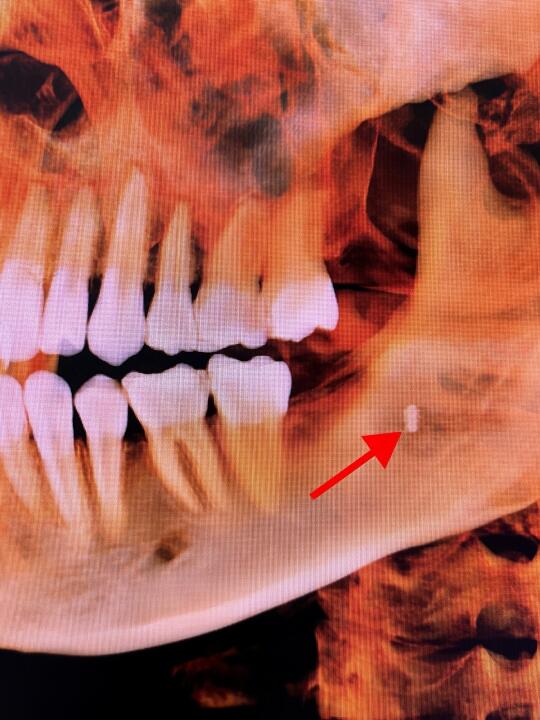

这张CT片,让多少人看的头皮发麻!